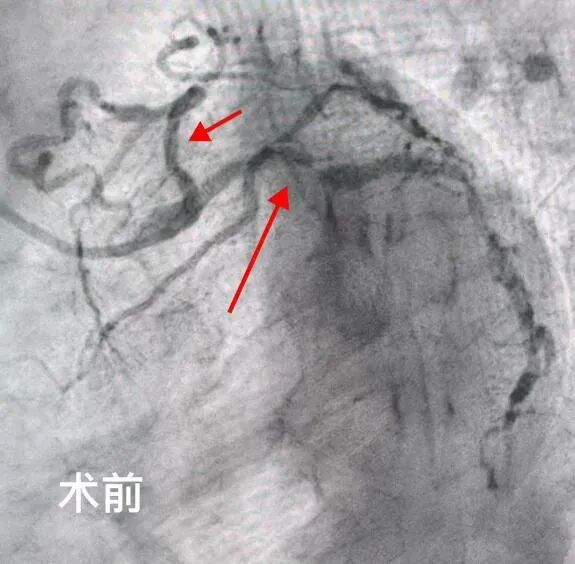

2025年5月,吉林市人民医院心内五病区收治了一位70岁的老年女性患者。该患者反复心绞痛1年,近3天症状加重。入院后,冠脉造影检查明确显示其存在严重的三支血管病变。通常情况下,冠脉搭桥手术是此类患者的首选治疗方案,但家属综合考虑患者年龄和身体状况,最终选择冠脉介入治疗。经心内五病区张金子主任团队审慎评估,决定分两次为患者实施支架植入术。

第一次手术顺利完成,在患者右冠状动脉植入两枚支架,心绞痛症状有所缓解,但仍反复发作。经过两周的精心调整,5月25日,患者再次入院接受第二次支架植入手术。然而,术后返回病区时,患者突发严重并发症——因剧烈恶心呕吐,吐出大量鲜血。由于患者既往有慢性胃炎病史,这一突发状况导致其病情急剧恶化,生命危在旦夕。 专 家 介 绍 吉林市人民医院心血管内科五病区主任 熟练处理各种疑难复杂病变,急性心梗介入治疗,慢性闭塞病变(CTO),左主干病变,分叉病变,血栓病变,口部病变,迂曲钙化病变,桥血管病变等介入治疗,熟练掌握各种分叉支架术式(crush,cullote),IABP(主动脉球囊反搏泵)辅助下高危病人介入治疗,IVUS(血管内超声),OCT(光学相关断层扫描技术)及FFR(冠脉血流储备检查)等各种设备及腔内影像学检查,为一名成熟独立术者。 以第一申请人申请市级课题一项;共发表论文11篇,其中核心期刊4篇;参与“国家级自然基金”课题1项;2018年于北部战区总医院心内科完成冠脉介入基地学员培训并获得冠脉介入资质证书;2020年于北部战区总医院心内科完成心血管专科医师培训,同年取得中国医师协会颁发的专科医师规范化培训合格证书。2022年于北部战区总医院心内科完成培训并获得结构性心脏介入资质证书。 吉林市昌邑区人大代表;吉林省老年心血管预防康复委员;吉林省中西医结合学会第一届心衰防治与康复专业委员会委员;2022年昌邑区十九届人民代表大会代表;2022年度吉林市昌邑区优秀人大代表;2022年吉林市统战最美统战人新阶层创新之星;2023年度吉林市昌邑区优秀人大代表。